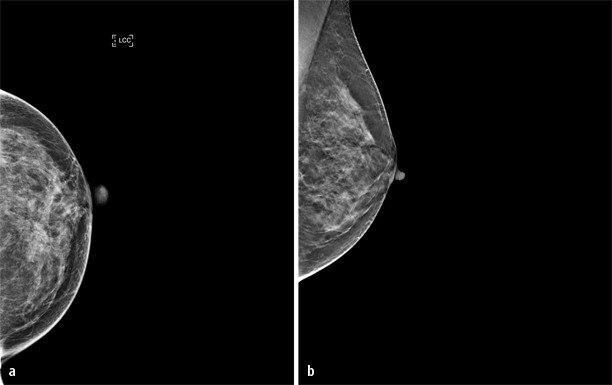

Anschließend tastet er die Brust sorgfältig ab und ordnet gegebenenfalls bildgebende Verfahren an, denn Gewebeveränderungen in der Brust lassen sich in der Regel gut mit Ultraschall (Sonographie) oder einer Mammographie darstellen Um einen bösartigen Tumor auszuschließen, entnimmt der Arzt meist eine Gewebeprobe. Das Sarkom befallen ist Weichteilgewebe der Brust, z B Binde, Fett oder Lymphgewebe Brustkrebs Entstehung Brustkrebs entsteht meist in den obersten Schichten der Milchgänge, wo sich Zellen besonders rasch teilen (duktales Mammakarzinom) Der Tumor kann aber auch von den Drüsenläppchen ausgehen (lobuläres Mammakarzinom). Want to learn how to play guitar?.

Anschließend tastet er die Brust sorgfältig ab und ordnet gegebenenfalls bildgebende Verfahren an, denn Gewebeveränderungen in der Brust lassen sich in der Regel gut mit Ultraschall (Sonographie) oder einer Mammographie darstellen Um einen bösartigen Tumor auszuschließen, entnimmt der Arzt meist eine Gewebeprobe. None of 17 patients with malignant brain tumors, leukemia or Hodgkin's disease, sarcoma or thyroid carcinoma reacted The DTHRT was specific in that all 77 healthy persons and 48/49 with other diseases, including 23/24 with noncancer lung disease were negative;. Solide Tumore sind in der Regel abnorme Gewebemassen, die keine Zysten oder Flüssigkeitsbereiche enthalten Sie können gutartig oder bösartig sein Obwohl diese Tumore im ganzen Körper auftreten, sind sie meist in Brust, Leber und Achselhöhlen zu sehen Solide Tumore werden nach der Art der Zellen benannt, aus denen sie sich zusammensetzen.